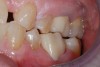

After the patient was anesthetized, the failing alloy restoration was removed along with the recurrent decay. A buildup was placed using bulk-fill composite and an adhesive bonding agent. Following preparation (Figure 4 and Figure 5), a No. 1 cord was placed in the sulcus, and then the preparation, working quadrant, opposing quadrant, and bite were scanned using an intraoral scanner.

(4.) Preparation.

Figure 4

(5.) Preparation.

Figure 5